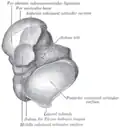

The body features several prominent articulate surfaces: On its superior side is the trochlea tali, which is semi-cylindrical,[6] and it is flanked by the articulate facets for the two malleoli.[3] The ankle mortise, the fork-like structure of the malleoli, holds these three articulate surfaces in a steady grip, which guarantees the stability of the ankle joint. However, because the trochlea is wider in front than at the back (approximately 5–6 mm) the stability in the joint vary with the position of the foot: with the foot dorsiflexed (toes pulled upward) the ligaments of the joint are kept stretched, which guarantees the stability of the joint; but with the foot plantarflexed (as when standing on the toes) the narrower width of the trochlea causes the stability to decrease.[7] Behind the trochlea is a posterior process with a medial and a lateral tubercle separated by a groove for the tendon of the flexor hallucis longus. Exceptionally, the lateral of these tubercles forms an independent bone called os trigonum or accessory talus; it may represent the tarsale proximale intermedium. On the bone's inferior side, three articular surfaces serve for the articulation with the calcaneus, and several variously developed articular surfaces exist for the articulation with ligaments.[3]

The head of talus looks forward and medialward; its anterior articular or navicular surface is large, oval, and convex. Its inferior surface has two facets, which are best seen in the fresh condition.[8]

The medial, situated in front of the middle calcaneal facet, is convex, triangular, or semi-oval in shape, and rests on the plantar calcaneonavicular ligament; the lateral, named the anterior calcaneal articular surface, is somewhat flattened, and articulates with the facet on the upper surface of the anterior part of the calcaneus.[8]

The neck of talus is directed anteromedially, and comprises the constricted portion of the bone between the body and the oval head.[8]

Its upper and medial surfaces are rough, for the attachment of ligaments; its lateral surface is concave and is continuous below with the deep groove for the interosseous talocalcaneal ligament.[8]

The body of the talus comprises most of the volume of the talus bone (ankle bone). It presents with five surfaces; a superior, inferior, medial, lateral and a posterior:[8]

- The superior surface of the body presents, behind, a smooth trochlear surface, the trochlea, for articulation with the tibia. The trochlea is broader in front than behind, convex from before backward, slightly concave from side to side: in front it is continuous with the upper surface of the neck of the bone.

- the inferior surface presents two articular areas, the posterior and middle calcaneal surfaces, separated from one another by a deep groove, the sulcus tali. The groove runs obliquely forward and lateralward, becoming gradually broader and deeper in front: in the articulated foot it lies above a similar groove upon the upper surface of the calcaneus, and forms, with it, a canal (sinus tarsi) filled up in the fresh state by the interosseous talocalcaneal ligament. The posterior calcaneal articular surface is large and of an oval or oblong form. It articulates with the corresponding facet on the upper surface of the calcaneus, and is deeply concave in the direction of its long axis which runs forward and lateralward at an angle of about 45° with the median plane of the body. The middle calcaneal articular surface is small, oval in form and slightly convex; it articulates with the upper surface of the sustentaculum tali of the calcaneus.

- The medial surface presents at its upper part a pear-shaped articular facet for the medial malleolus, continuous above with the trochlea; below the articular surface is a rough depression for the attachment of the deep portion of the deltoid ligament of the ankle-joint.

- The lateral surface carries a large triangular facet, concave from above downward, for articulation with the lateral malleolus; its anterior half is continuous above with the trochlea; and in front of it is a rough depression for the attachment of the anterior talofibular ligament. Between the posterior half of the lateral border of the trochlea and the posterior part of the base of the fibular articular surface is a triangular facet which comes into contact with the transverse inferior tibiofibular ligament during flexion of the ankle-joint; below the base of this facet is a groove which affords attachment to the posterior talofibular ligament.

- The posterior surface is narrow, and traversed by a groove running obliquely downward and medialward, and transmitting the tendon of the Flexor hallucis longus. Lateral to the groove is a prominent tubercle, the posterior process, to which the posterior talofibular ligament is attached; this process is sometimes separated from the rest of the talus, and is then known as the os trigonum. Medial to the groove is a second smaller tubercle.